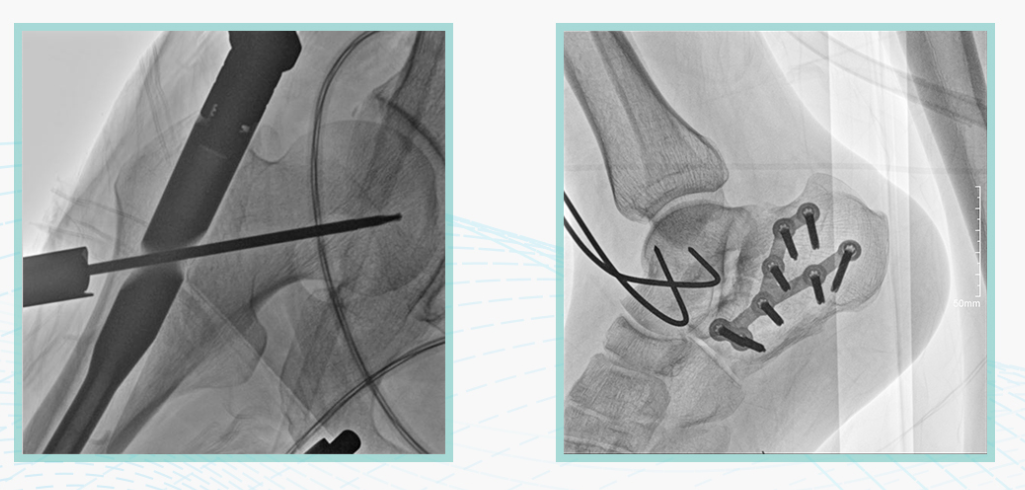

此外,骨科手术时间平均时长约为45分钟左右时间,长期的X线透视或摄影曝光剂量将对临床手术与操作医务工作者造成难以评估的健康风险,悦画通过支持摄影曝光参数的自主调节,可以保证在最低剂量水平下输出满足临床手术定位与引导所需要的影像质量,相较于市面上的固定曝光参数配置移动C臂,自主参数调节设计的曝光功能设计,可以大幅减少医务工作者的X线辐射剂量。

不仅如此,悦画在产品的剂量安全管理上,还支持DAP剂量实时显示与统计功能。为了减少误操作的X射线曝光,悦画具有X射线锁定保护功能,在摄影曝光停止后立即进行X射线曝光锁定,解锁后才能支持继续曝光,减少以往临床过程中医务工作者因为误操作所导致的额外X射线辐射。

悦画在影像的伪影处理上,也积累多项图像处理专利技术。通过对植入物的精准识别,悦画能够精准祛除植入物伪影与运动伪影,保证高质量的影像输出,无论是影像的对比度、分辨率(清晰度)相较于市面上的移动C臂产品都更胜一筹。